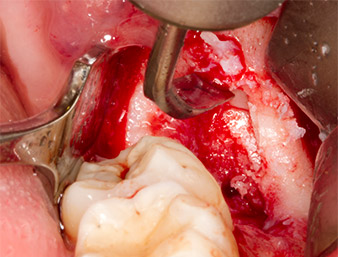

After block and local anaesthesia, the operating site was opened up and the soft tissue exposed for buccal retromolar access (Fig. 3).

sulcular incision

Fig. 3: The sulcular incision begins in mid-tooth 36 (LL6), with distal extension on the ascending ramus.